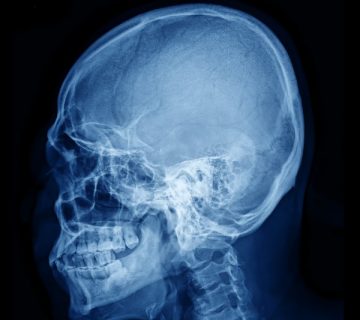

La cirugía se utiliza frecuentemente para tratar los cánceres de laringe. Dependiendo del tipo, la etapa y la localización del cáncer, así como de otros tejidos afectados, se pueden emplear diferentes operaciones para extirpar el cáncer y algunas veces otros tejidos cercanos a la laringe. En casi todas las cirugías, el plan es extraer todo el cáncer junto con un borde (margen) de tejido sano que lo rodea.

Las técnicas quirúrgicas incluyen la resección de una cuerda vocal (cordectomía), parte o toda la laringe supraglótica, una hemilaringe en sentido vertical o, en ocasiones, cuando no es posible conservar un segmento anatómico y funcional de la laringe, una laringectomía total. Dependiendo de la localización dentro del órgano y de la extensión del tumor, se realiza la extirpación de las áreas de drenaje ganglionar relacionadas con la localización tumoral.